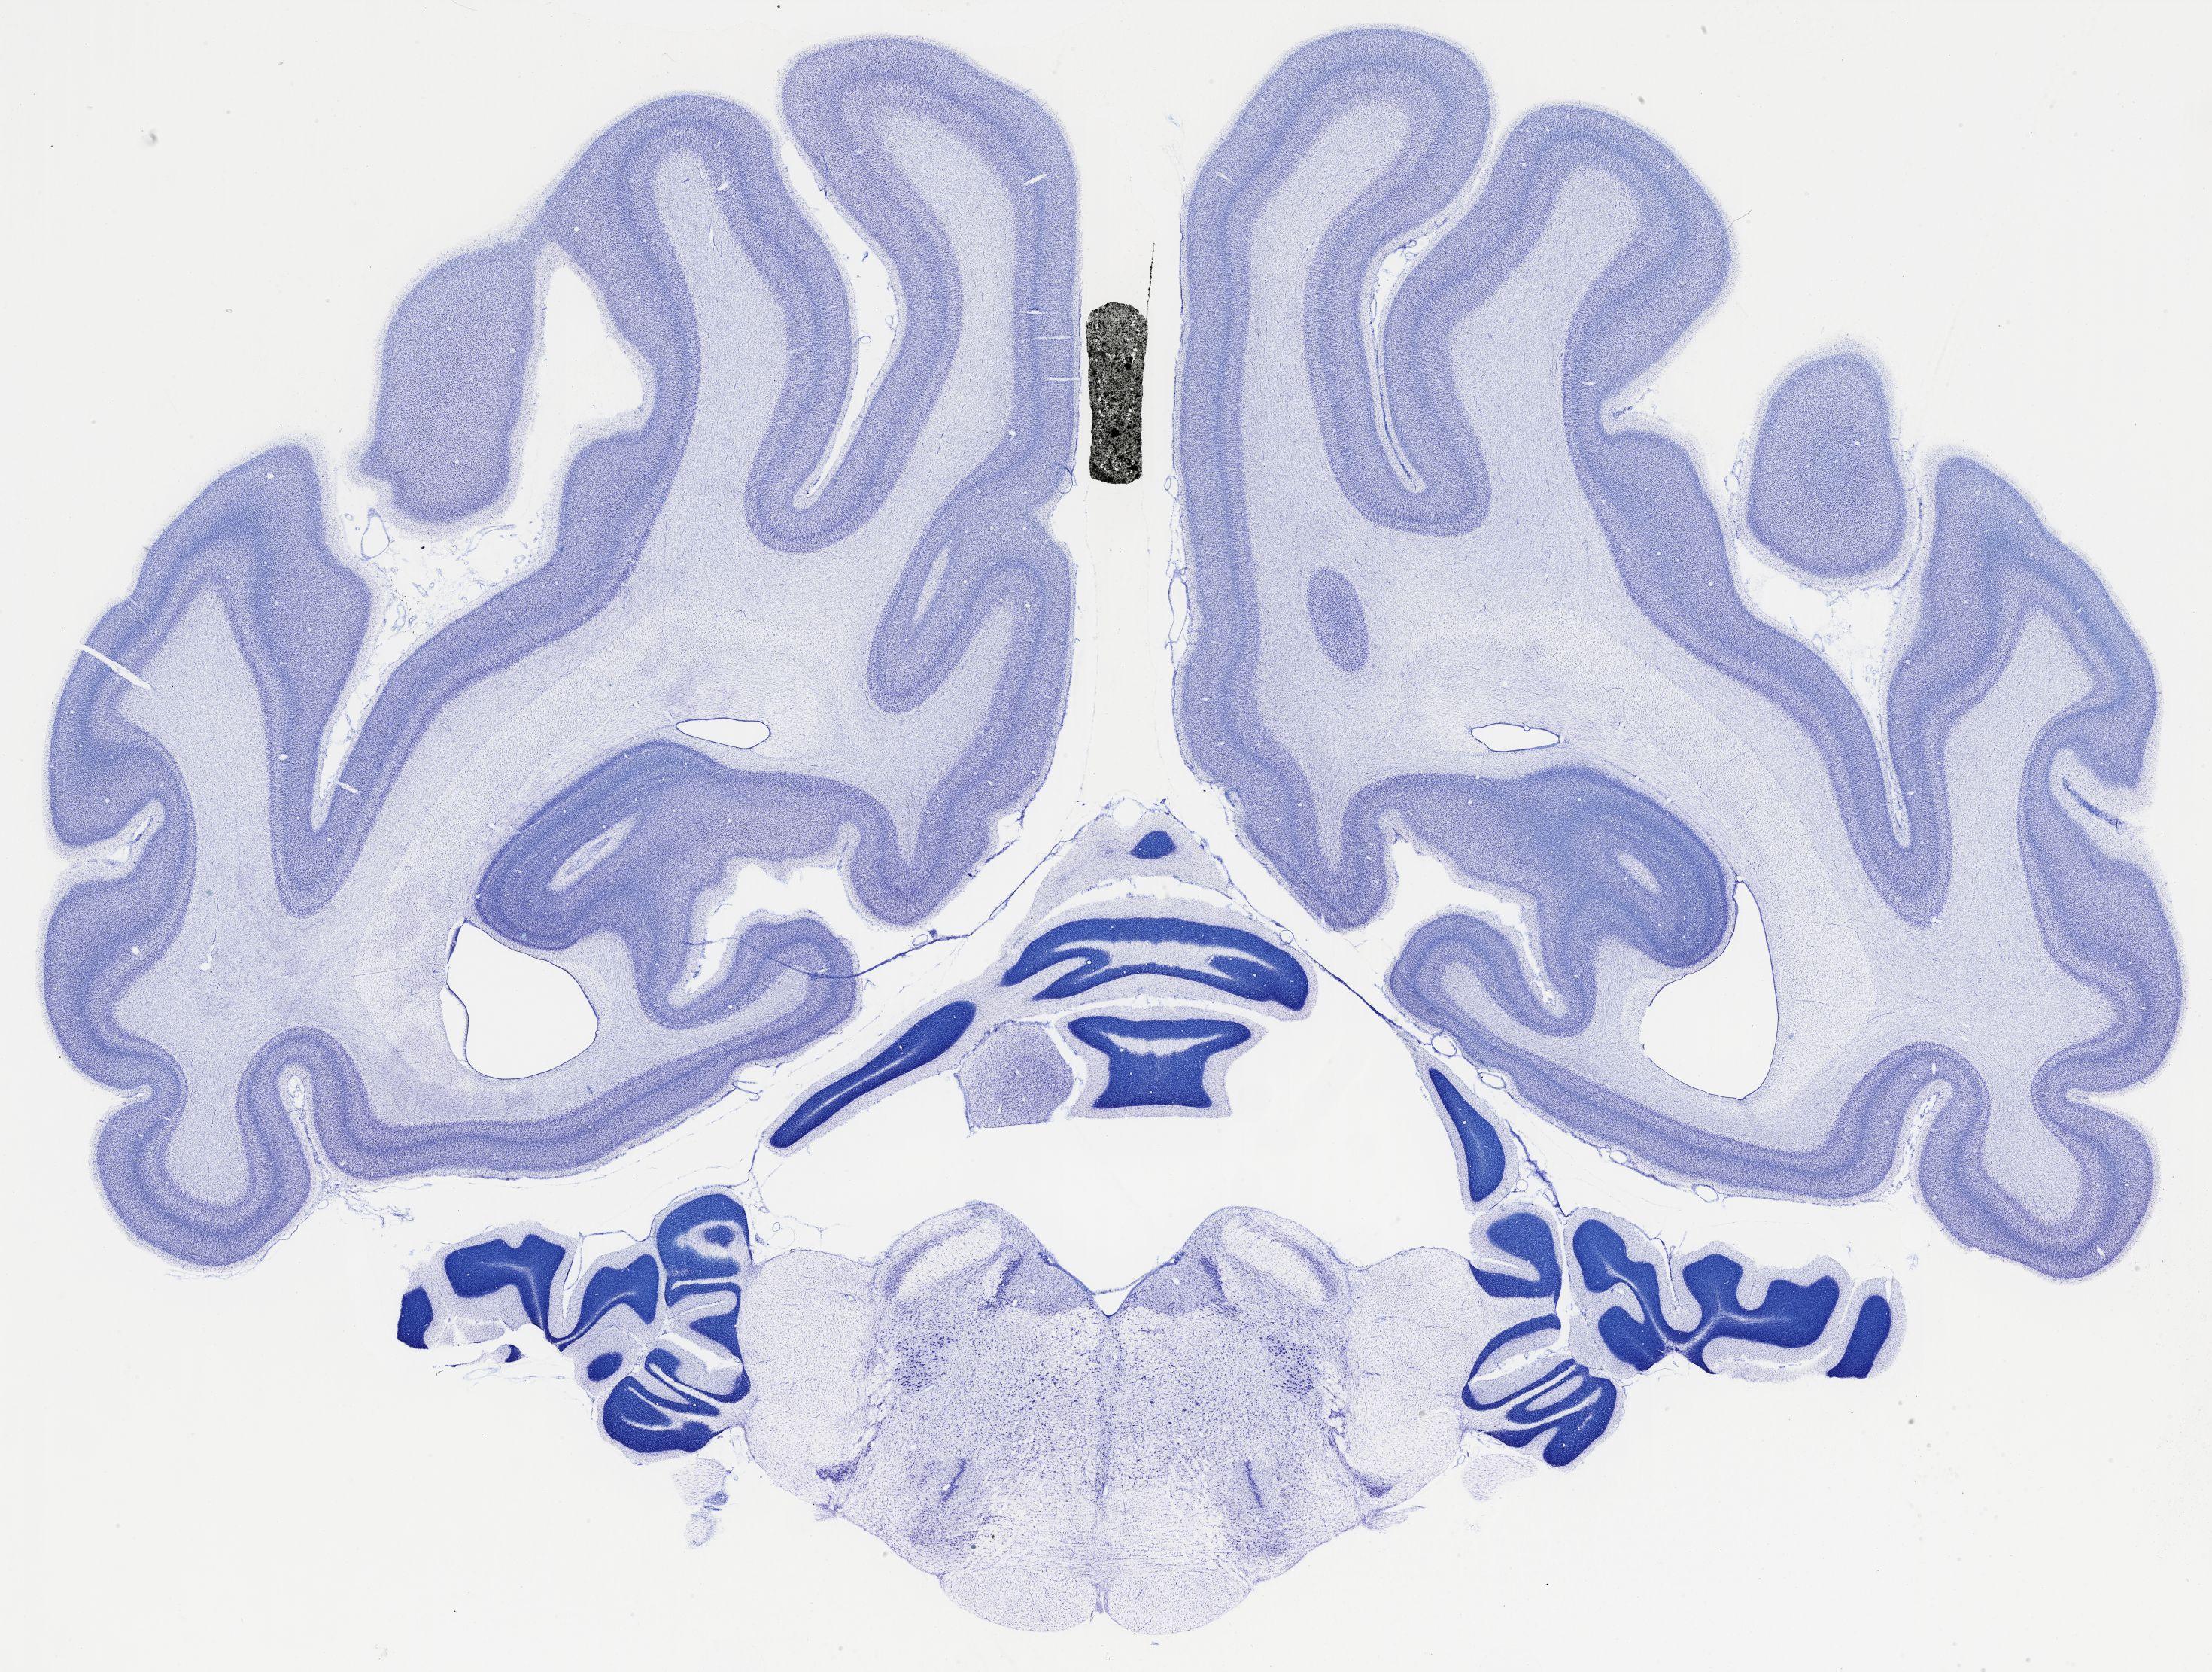

Datasets -> Chlorocebus Aethiops -> Nissl, coronal, histo, Whole-Brain, adult

[ Metadata ]   ·   Source: NeuroScience Associates

thumbnail

523